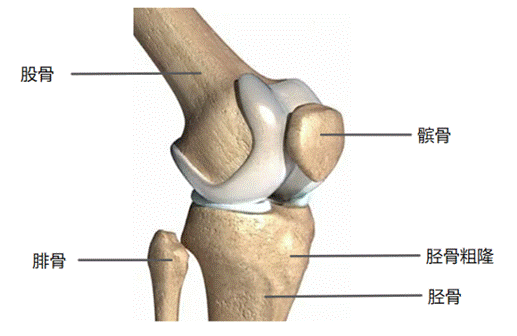

3)冠状位(自前向后)

前交叉韧带起自胫骨髁间棘前方,斜向后外上走行,止于股骨外侧髁内侧面。后交叉韧带起自胫骨髁间棘后方,斜向前内上走行,止于股骨内侧髁内侧面(斜十字相交,如图④)。